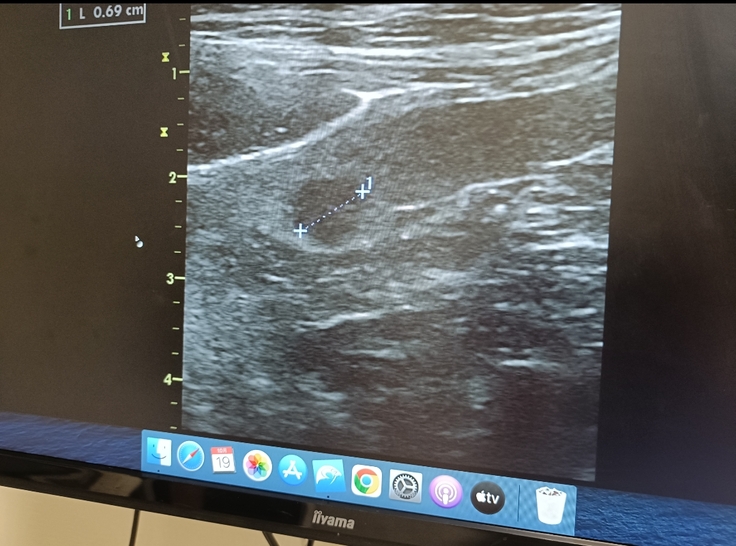

添い寝しながらあちこち撫でていると…喉にしこりを見つけてしまいました。

喉のしこりに関しては1cm以下で、このサイズだとほとんどの飼い主さんは気づかないらしく「よく見つけたね」と先生に声をかけて頂けました。